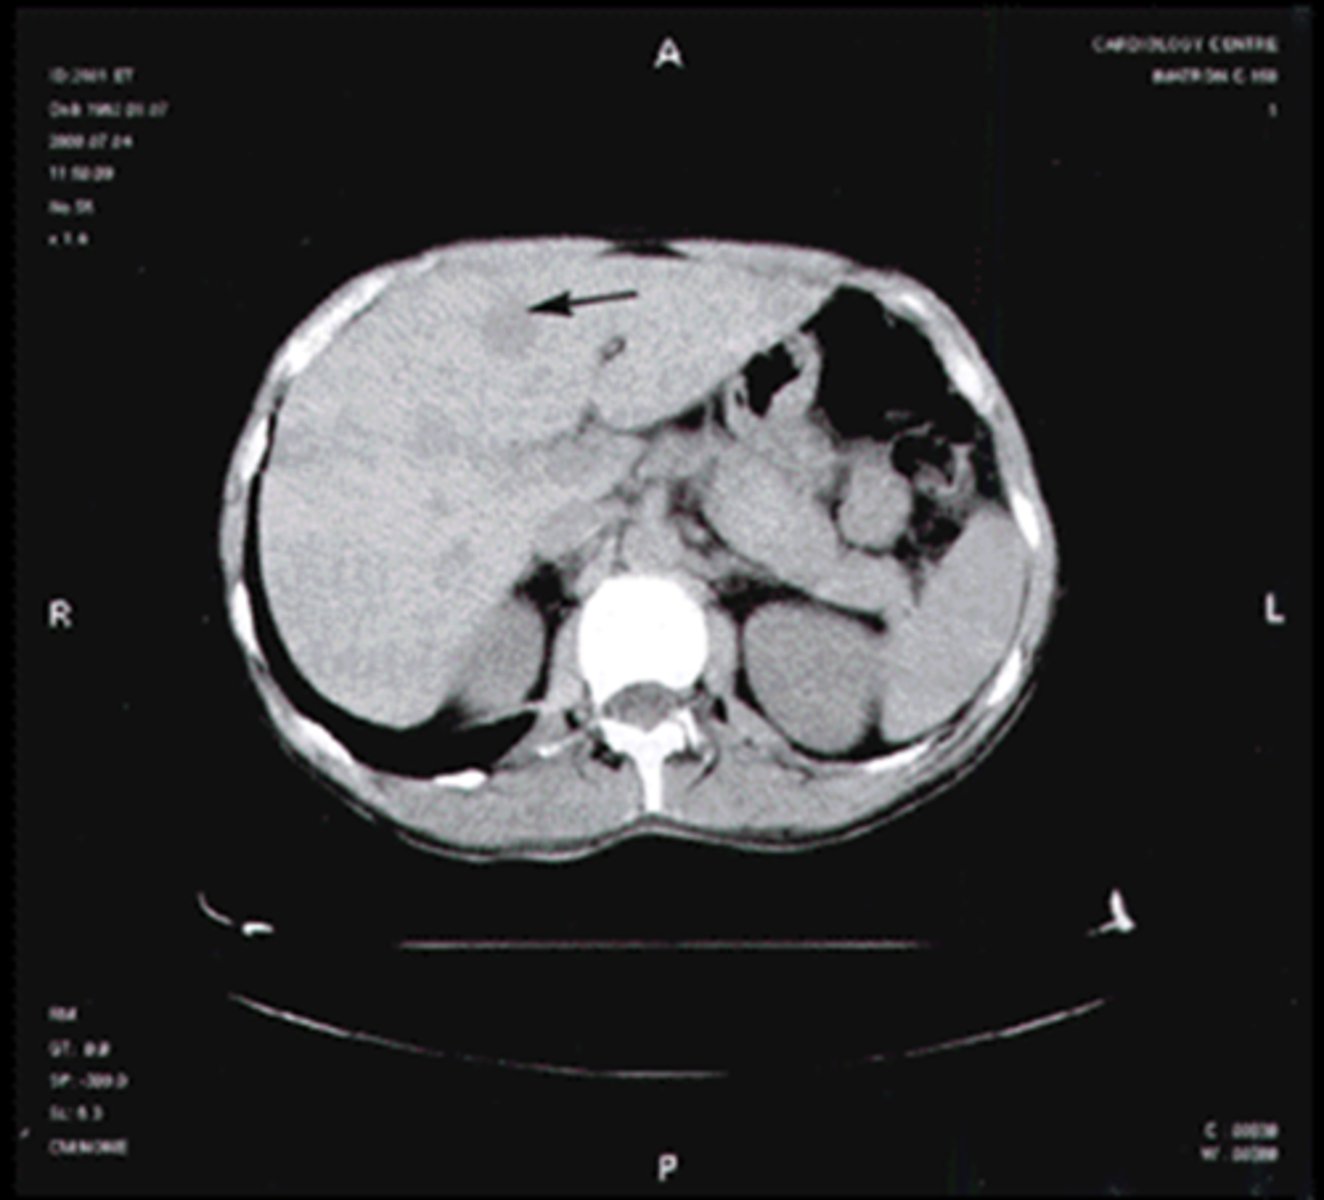

fatty liver

focal or diffuse fatty infiltration appears as less dense on CT

liver trauma

most injured intra-abdominal organ, lacerations and hemorrhages often seen

hemangioma

most common benign hepatic tumor, often found incidentally on US and CT, looks like normal liver with contrast

hepatoma

most common primary malignant hepatic tumor

hepatic cysts

common, usually incidental findings, lower density than liver, clearly defineed

hepatic abscess

localized collection of pus, low density lesion